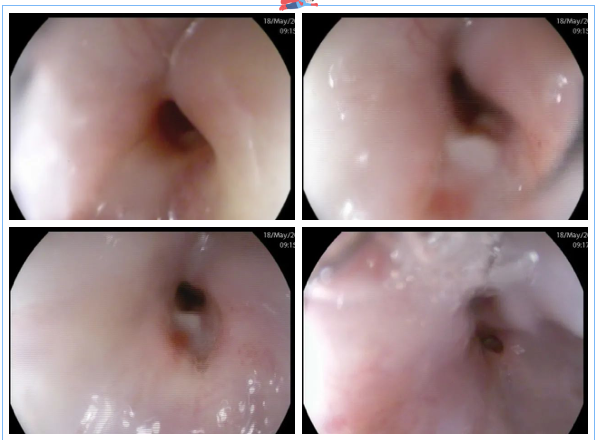

這時(shí),3診是一位懷疑食管瘺的患者,進(jìn)鏡至距門齒約25cm見食管管腔狹窄明顯,無法繼續(xù)進(jìn)鏡,狹窄處黏膜粗糙、色紅,可見潰瘍形成。嘗試給予胃營養(yǎng)管置入,插至距門齒約35cm處阻力過大,反復(fù)嘗試后,無法留置。